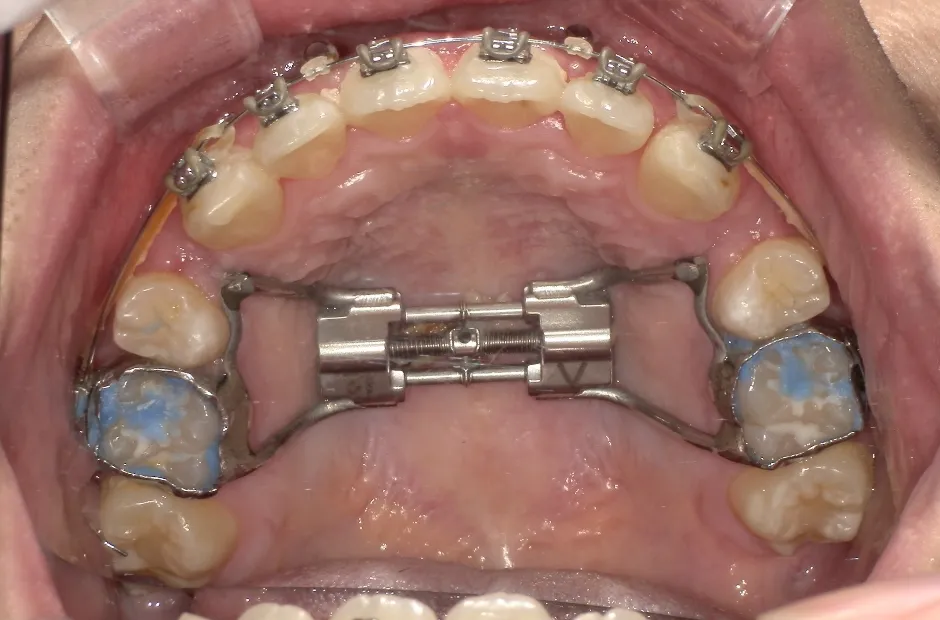

ゆがみ(左右非対称)

| 診断名・主訴 | ゆがみ(左右非対称) |

|---|---|

| 年齢・性別 | 20歳・女性 |

| 治療期間・回数 | 2年半 30回 |

| 治療に用いた主な装置 | 急速拡大 アンカー |

| 抜歯部位 | 左右上5番 |

| 治療費 | 70万円(税抜) |

| リスク・副作用 | 装置による違和感・疼痛・歯肉退縮・歯根吸収・虫歯のリスクなど |

治療前